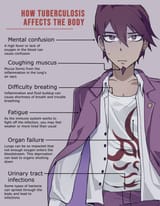

Ranking how despairing their backstories are

No.538138983

I've seen smokers who are perfectly healthy because they also routinely workout, not being a total addict and know when to stop once they reach 50.